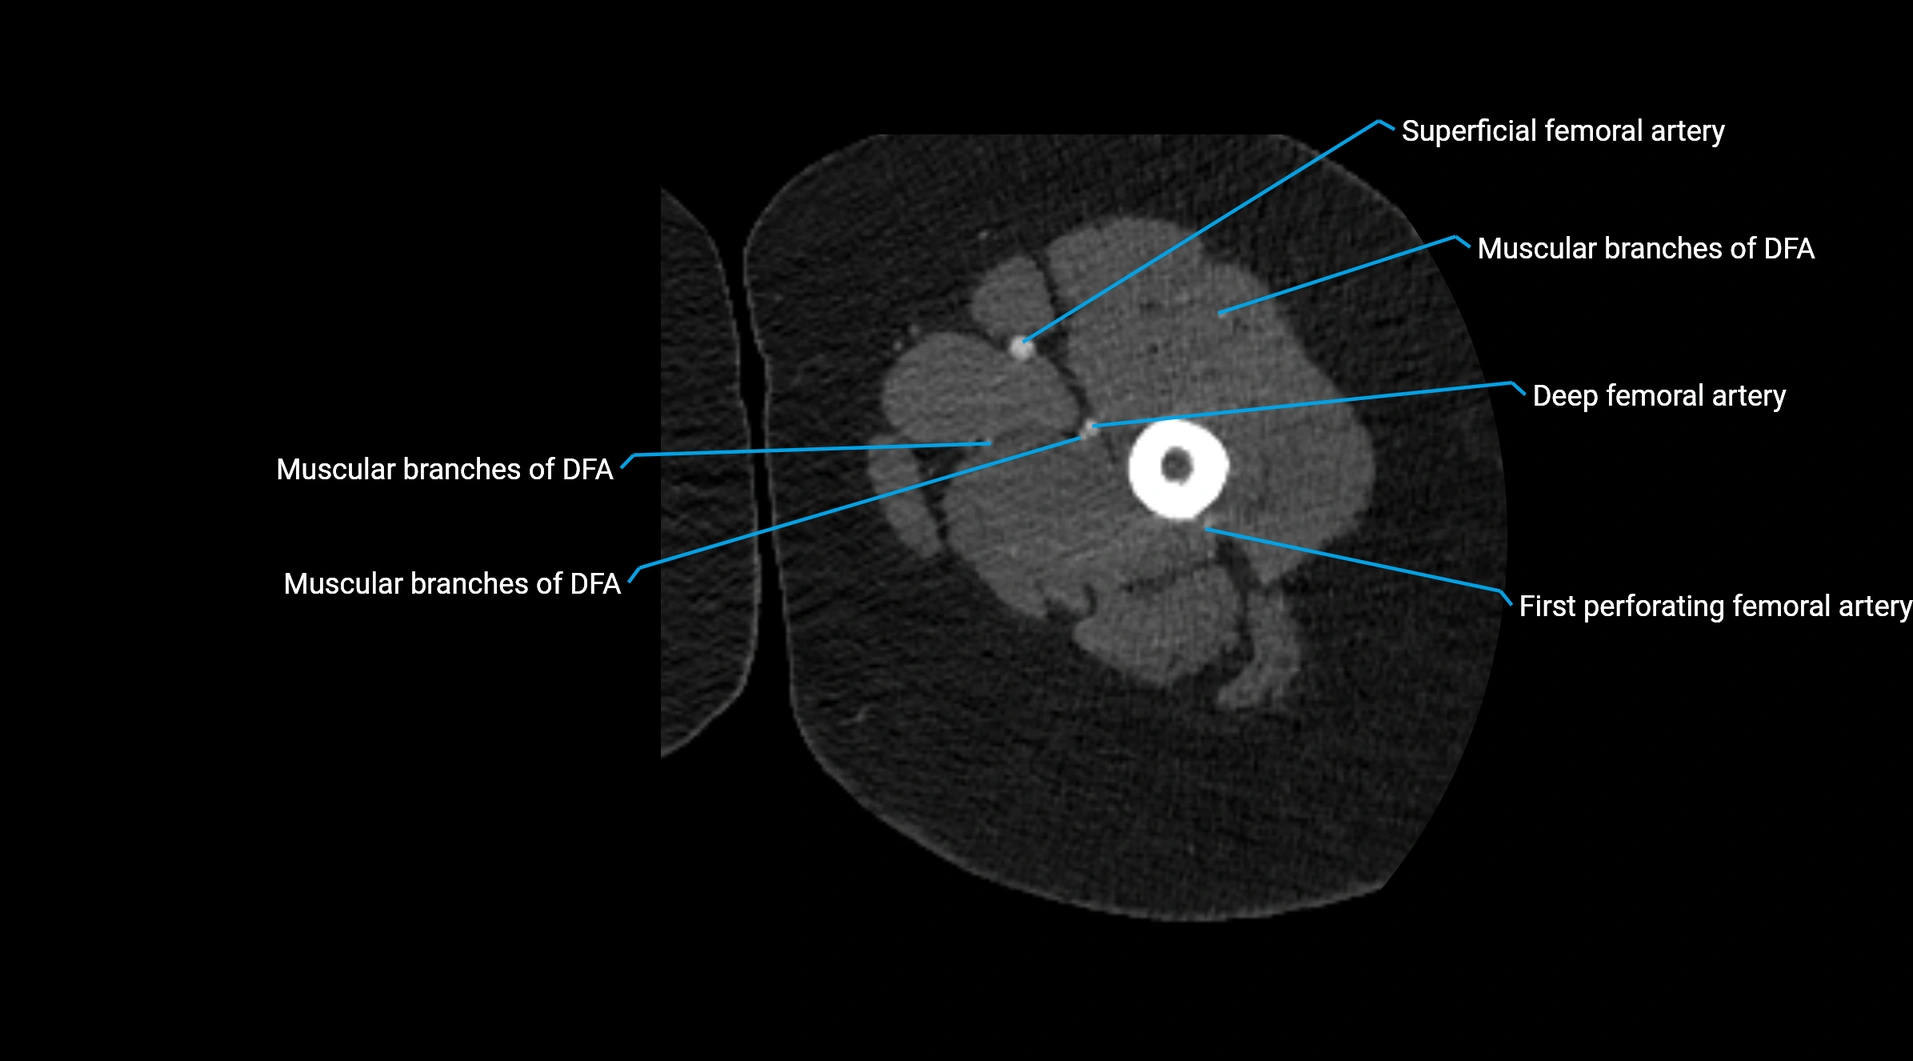

Contrast-enhanced CT (CTA):

• Gold standard for abdominal aortic imaging

• Provides excellent detail of lumen, wall, aneurysm, thrombus, and branch vessels

• Multiplanar and 3D reconstructions help in aneurysm measurement, stent graft planning, and dissection evaluation